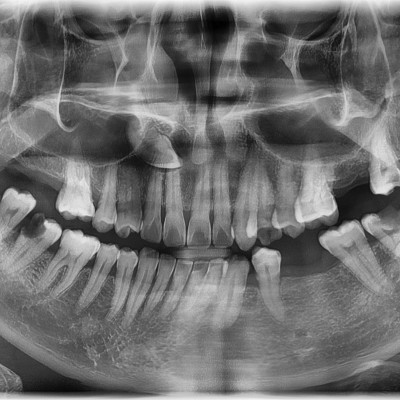

#28,38 사랑니 발치 #28,38 사랑니 발치 구강 외과 전문의가 당일 발치했습니다. --------------------------..

작성자 이턱이 작성일 03-11 조회 23